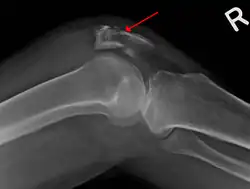

The patella can break in various ways depending on the way it is injured, and into two or more pieces.[1] Types include transverse, the most common, with one fracture line;[5] marginal; osteochondral; and the rare vertical type, or stellate, where a direct compression force gives rise to a comminuted pattern.[5][7] Patella fractures can be further classified as displaced, where the broken ends of bone do not line up correctly and separate by more than 2mm, or undisplaced and stable where pieces of bone remain in contact with each other.[1][7] If fragments of patella bone stick out from the skin it is known as an open patella fracture, and closed if the overlying skin is intact.[1]

Transverse fracture of patella -